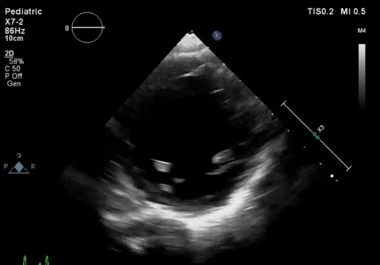

心エコー図

急性心筋炎の典型的な所見は,炎症部位に一致した浮腫状の壁肥厚,壁運動低下,内腔狭小化,心膜液貯留で,炎症が消退し急性期を過ぎれば回復に至る例が多い.発症初期には機能低下が軽度でも経時的に悪化する場合や,心腔内血栓を生じる例もあり,厳重なモニタリングを要する.左室収縮能は保たれるものの房室伝導障害が病態の主体である例,左室腔拡大や壁菲薄化,収縮低下から拡張型心筋症と判別できない例もある.多くは左室優位に機能低下を来すが,右室優位の心筋炎も時にみられる.自験例をMovie 1に示す.

慢性活動性心筋炎や慢性炎症性心筋症では左室拡大,びまん性の壁運動低下を来すことが多く,拡張型心筋症と同様の所見を呈する.

Movie 1-C